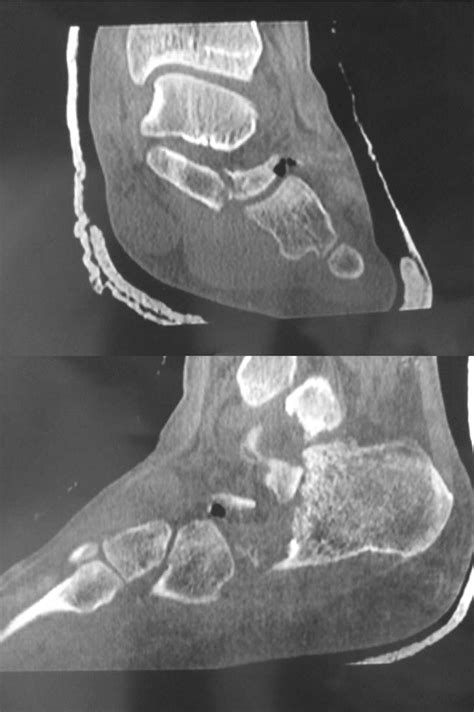

The Vacuum Disc Phenomenon describes the presence of gas, primarily nitrogen, within the intervertebral discs of the spine. When you look at an imaging study, this appears as a dark, linear, or localized radiolucency within the disc space. Essentially, it is a sign that the disc is undergoing degeneration or drying out.

The intervertebral discs act as shock absorbers between your vertebrae. Healthy discs are hydrated and flexible. As we age, these discs lose their water content, become thinner, and shrink. When a disc loses enough volume, a negative pressure, or "vacuum," is created within the disc space. This pressure drop causes nitrogen gas—which is normally dissolved in our body fluids—to pull out of the surrounding tissues and collect in the disc, forming what we see on the imaging as the Vacuum Disc Phenomenon.